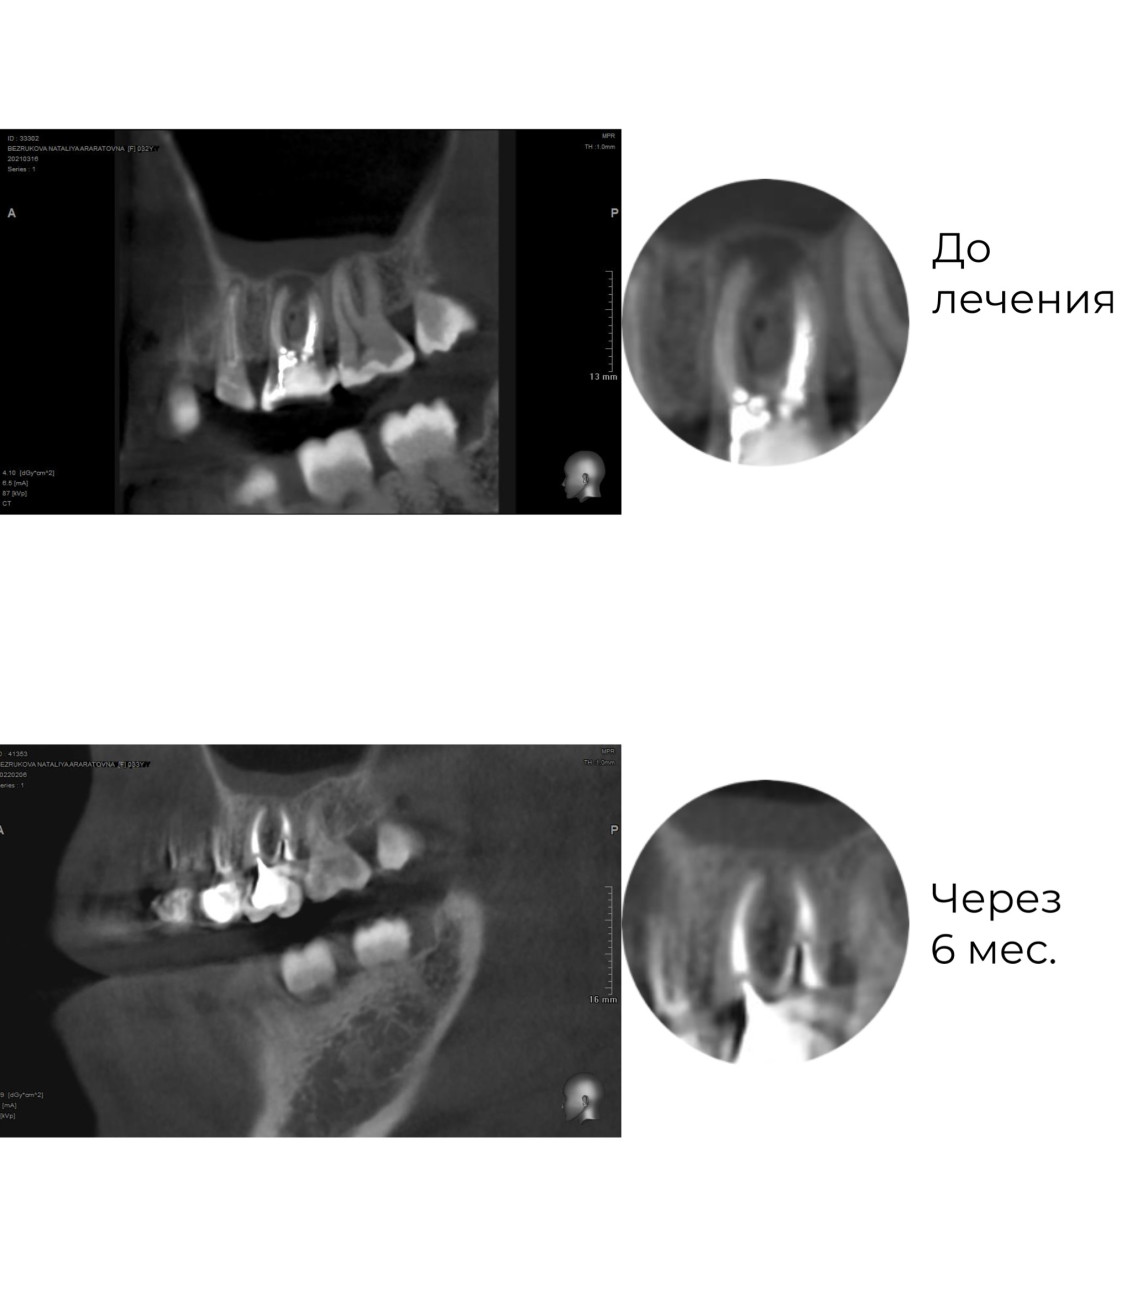

Лечение кист, периодонтита